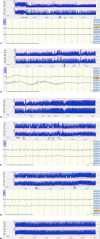

Methods: Retrospective cohort study of near term neonates admitted to the neonatal intensive care unit with EEG-confirmed seizures despite treatment with PB as first-line therapy and using LEV as 2nd-, 3rd- or 4th-line treatment. Antiseizure medication was administered according to national guidelines. All neonates were monitored with 2-channel amplitude-integrated electroencephalography. The total seizure burden in minutes, 2 h before and 4 h after administration of LEV, was calculated using raw EEG. Primary outcome was the efficacy of LEV in achieving >80% seizure reduction. The efficacy of additional midazolam (MDZ) and lidocaine (LDC) was also calculated.